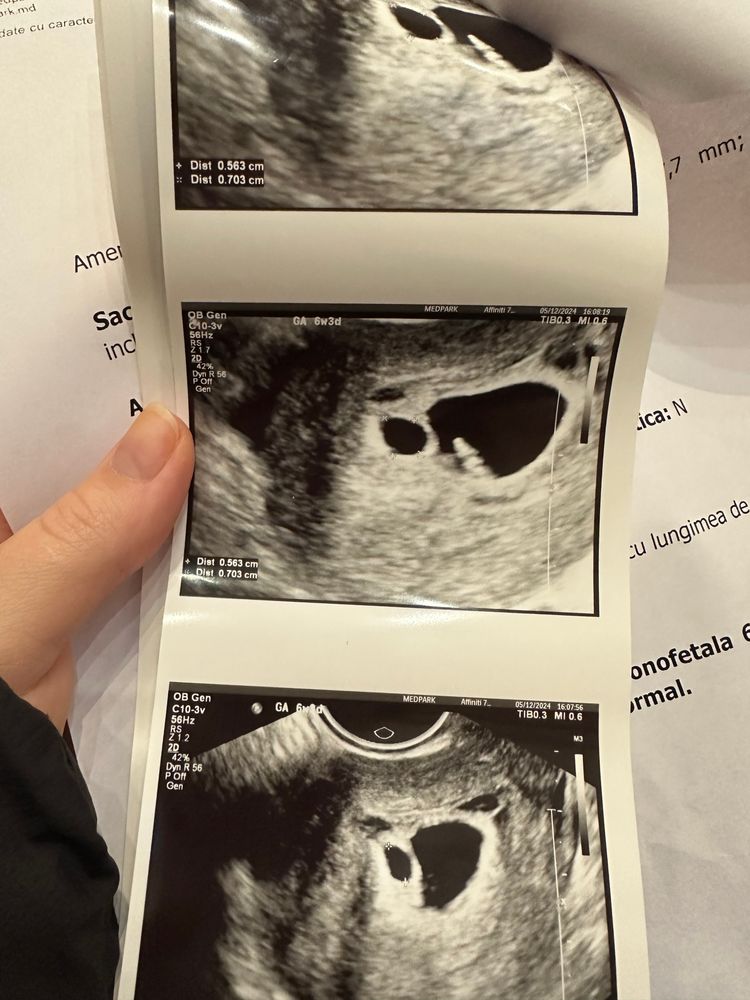

24 дпп первое узи УЗИ 21 дпп